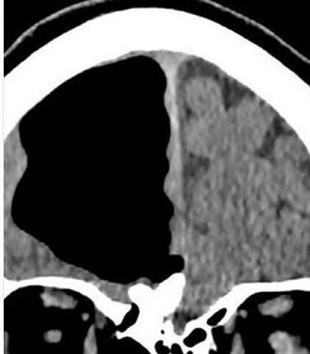

Baş ağrısının yanı sıra sol tarafında bir ağrı ve yürümede sıkıntı yaşayan hastanın röntgeni kısa sürede çekildi. Fakat doktorlar röntgeni inceledikten sonra tıp tarihinde eşi benzerine çok zor rastlanan bir sonuçla karşılaştı. Doktorlar, 84 yaşındaki hastanın beyninin sol tarafının olmadığını fark etti.

Hayatı boyunca sigara içmeyen ve nadiren alkol alan adamda görüş bozukluğu, konuşma ya da görsel rahatsızlıkları olmadığını açıklayan doktorlar, “O günlük fiziksel aktivitelerini aksatmadan yapan, sağlıklı bir haldeydi. Fakat yapılan testler sonucunda biz de çok şaşırdık” ifadesini kullandı.